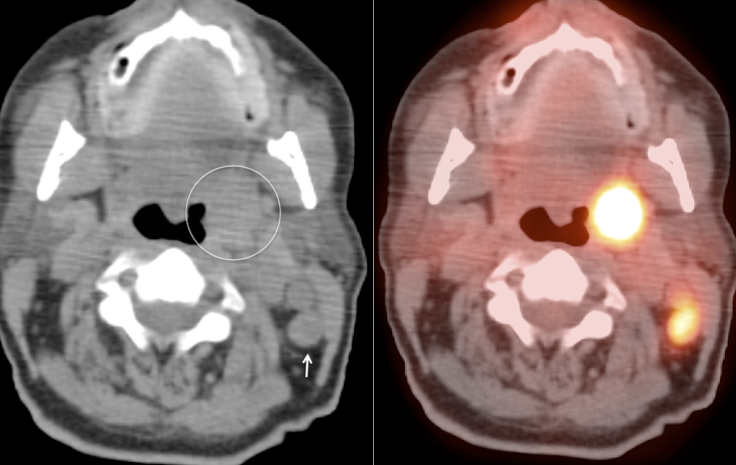

Symmetric, Bilateral Tonsillar Uptake:

The palatine tonsils frequently demonstrate significant metabolic activity.

Bilateral and fairly symmetric FDG-uptake in non-enlarged palatine tonsils is typically a normal finding, and is usually not mentioned in a report.

Bilateral and fairly symmetric FDG-uptake in enlarged palatine tonsils is nearly always inflammatory in nature (although can be seen with lymphoma).

Unilateral FDG-Avid Tonsil (or Relative Increased Avidity of One Tonsil):

Special care is required when assessing the incidental finding of a unilateral hot tonsil (or relative increased uptake within one tonsil) — even though most unilateral hot tonsils are benign. Proposed techniques for assessment have included SUV threshold cutoff values, metabolic tumor volume assessment, and SUV ratios.

Unfortunately, it is advisable to raise at least a degree of concern for most FDG-avid unilateral tonsillar findings. The level of suspicion, of course, depends on the presentation.